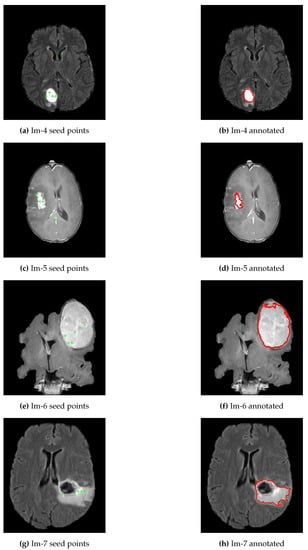

As presented in Algorithm 2, line 6 and Equation (1), the mean intensities for each of the 32 blocks were computed and selected only the top five brightest pixels as potential candidates to use as seed points for the region-growing segmentation algorithm, refer Figure 3a,c,e,g. Line 12 to 14 of Algorithm 2 presented the five ROIs generated by region-growing segmentation algorithm, and then compared the results against the ground truth using evaluation parameters to select the best ROI as a final segmentation output, see Figure 3b,d,f,h. The region-growing segmentation algorithm’s threshold point is determined experimentally to be 0.1 since most of the tumor regions appear homogeneous. However, some of the inhomogeneities parts were accommodated with fill hole operations as shown in Figure 3h. In this particular brain image, the tumor core appears black and our algorithm might detect only the boundaries. But, for such cases, we applied the fill holes operations to include the core of the tumor.

Figure 3.

Generated possible seed points and annotations using proposed approach. (a,c,e,g) represent a skull removed original brain images with five potential seed points for brain images; (b,d,f,h) represent the best ROIs of each respective brain images.

The first experimental result was the skull stripped brain images as indicated in Figure 2 where Figure 2a,c,e,g were the original brain images of size and Figure 2b,d,f,h were the skull stripped brain images. Then, as presented in Equation (1), we generated 32 average intensities for each skull stripped brain images and selected the five top average intensities for each image and used as potential initial seed points for region growing algorithm as indicated in Figure 3a,c,e,g. Using the five selected initial seed points for each image, we generated five different ROIs and compared against the respective GT and selected the best ROI as presented in Figure 3b,d,f,h.